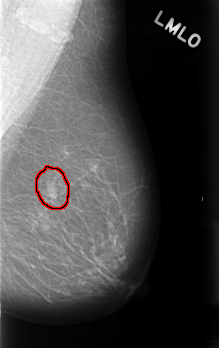

FILE: C_0454_1.LEFT_MLO.OVERLAY

TOTAL_ABNORMALITIES 1

ABNORMALITY 1

LESION_TYPE MASS SHAPE OVAL MARGINS CIRCUMSCRIBED

ASSESSMENT 3

SUBTLETY 5

PATHOLOGY BENIGN_WITHOUT_CALLBACK

TOTAL_OUTLINES 1

BOUNDARY

LEFT_MLO LINES 4520 PIXELS_PER_LINE 2840 BITS_PER_PIXEL 12 RESOLUTION 50 OVERLAY